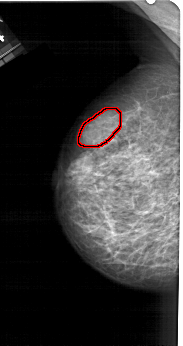

FILE: A_1279_1.LEFT_MLO.OVERLAY

TOTAL_ABNORMALITIES 1

ABNORMALITY 1

LESION_TYPE MASS SHAPE LOBULATED MARGINS CIRCUMSCRIBED

ASSESSMENT 4

SUBTLETY 2

PATHOLOGY BENIGN

TOTAL_OUTLINES 1

BOUNDARY

LEFT_MLO LINES 5176 PIXELS_PER_LINE 2731 BITS_PER_PIXEL 12 RESOLUTION 43.5 OVERLAY